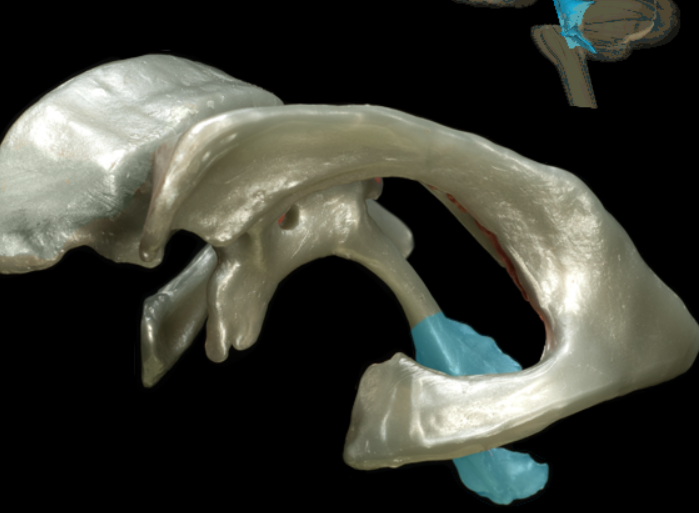

tentorium cerebelli